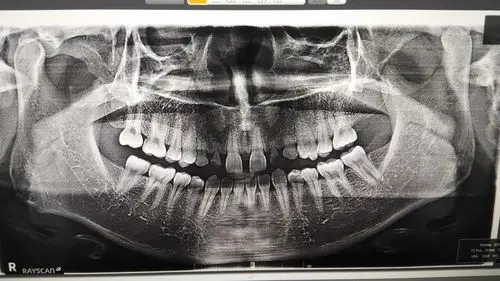

我刚长了智齿去牙科医院去看牙,拍完ct告诉我牙离下颌神经太近了,会有

牙科诊所拍的片子怀疑这两颗乳牙里面还有隐藏牙,需要我去大医院拍ct

左下侧尾齿蛀牙疼痛期间半年左右反复发作x光片显示牙齿下方有阴影

口腔ct片